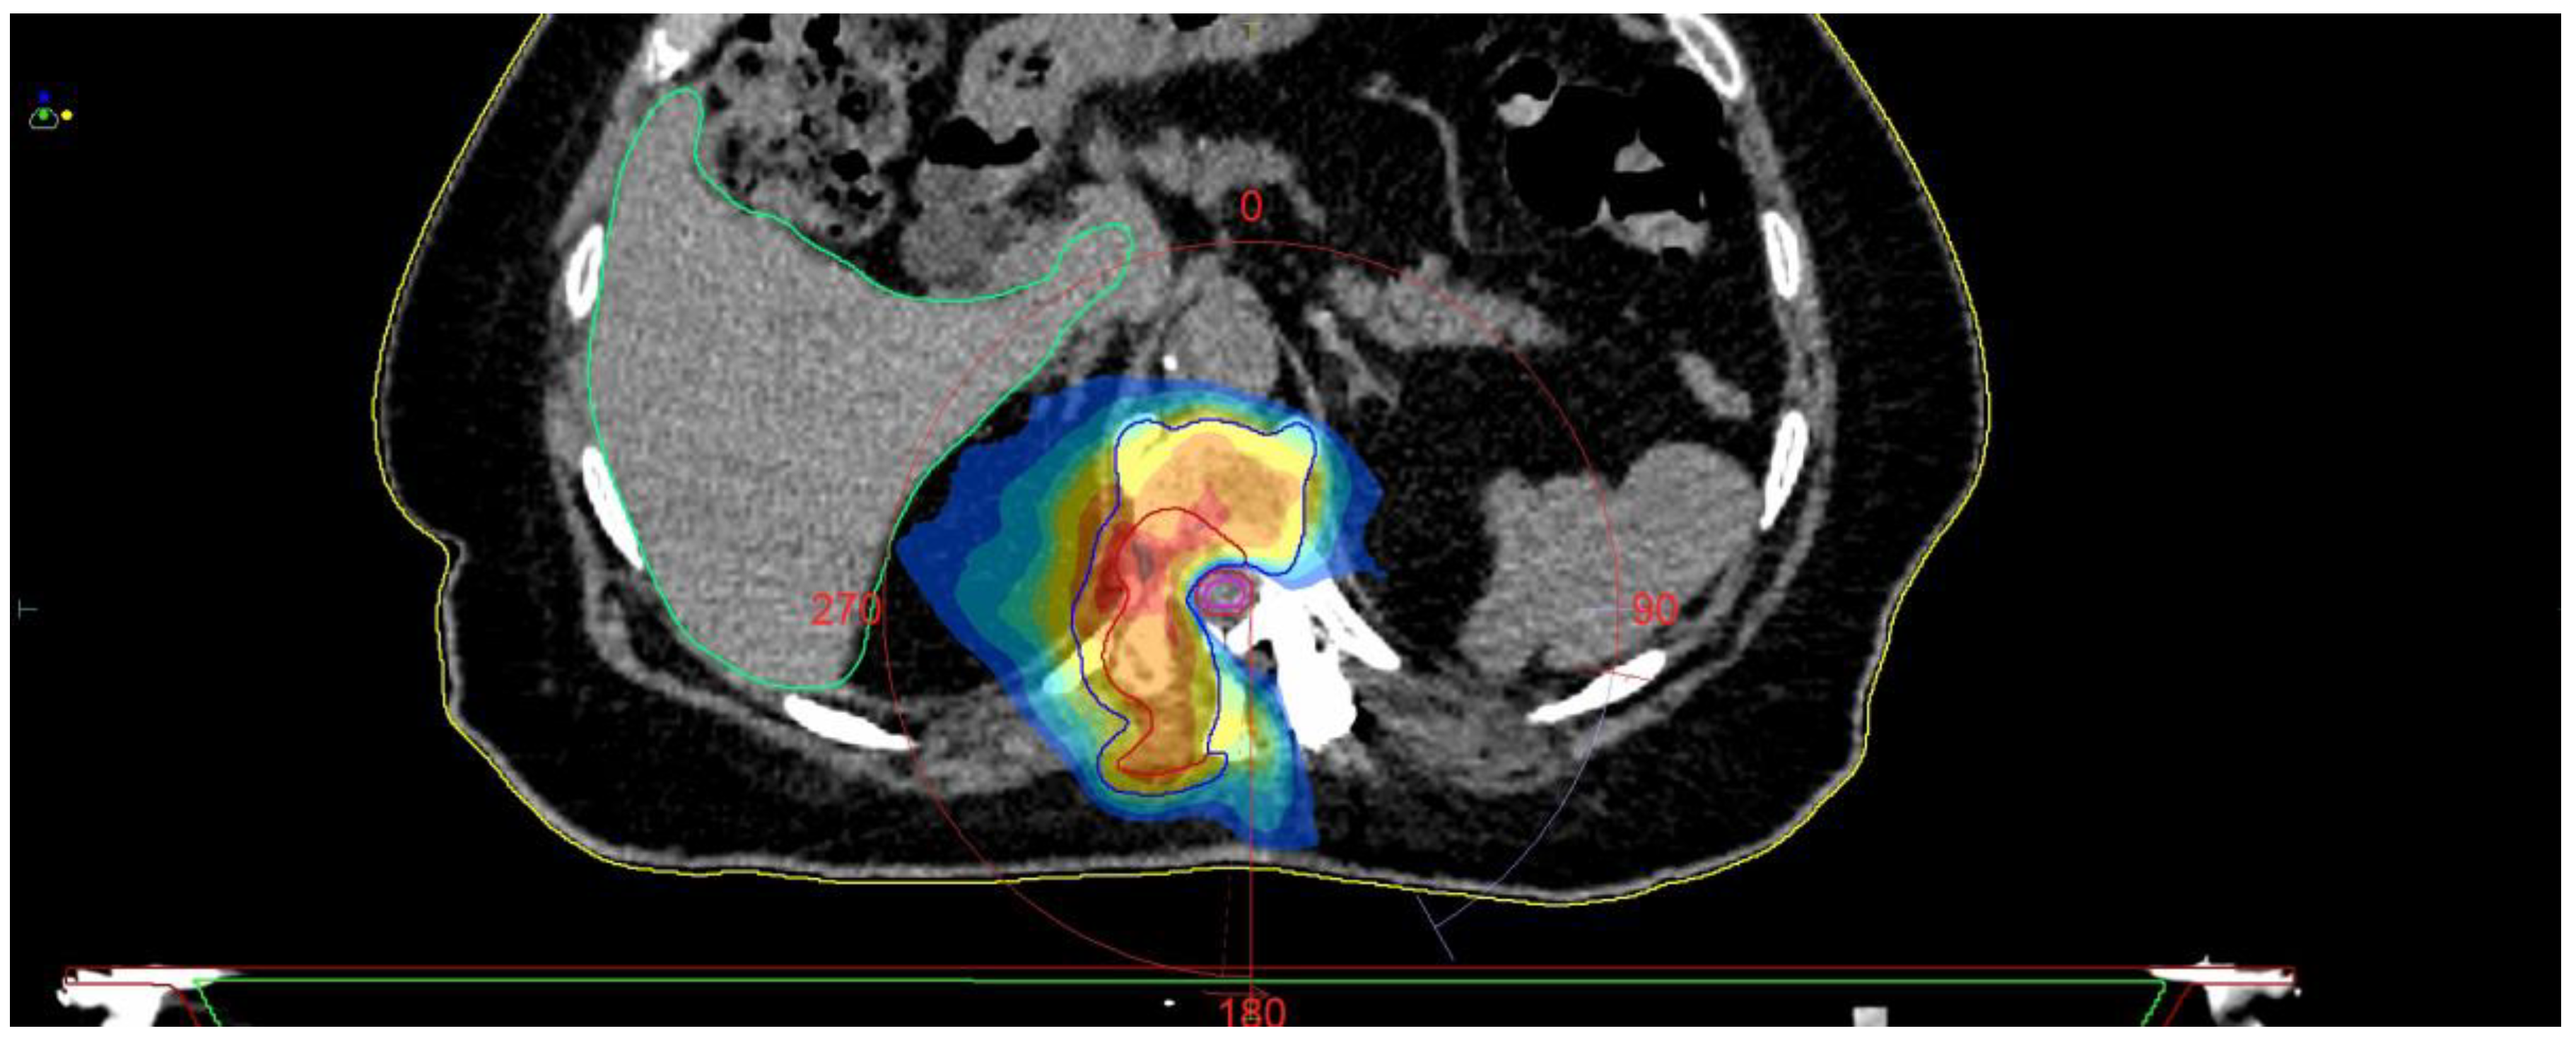

Fully Endoscopic Spine Separation Surgery in Metastatic Disease—Case Series, Technical Notes, and Preliminary Findings

- Di Perna, G.; Cofano, F.; Mantovani, C.; Badellino, S.; Marengo, N.; Ajello, M.; Comite, L.M.; Palmieri, G.; Tartara, F.; Zenga, F.; et al. Separation surgery for metastatic epidural spinal cord compression: A qualitative review. J. Bone Oncol. 2020, 25, 100320. [Google Scholar] [CrossRef]

- Cofano, F.; Di Perna, G.; Marengo, N.; Ajello, M.; Melcarne, A.; Zenga, F.; Garbossa, D. Transpedicular 3D endoscope-assisted thoracic corpectomy for separation surgery in spinal metastases: Feasibility of the technique and preliminary results of a promising experience. Neurosurg. Rev. 2020, 43, 351–360. [Google Scholar] [CrossRef]